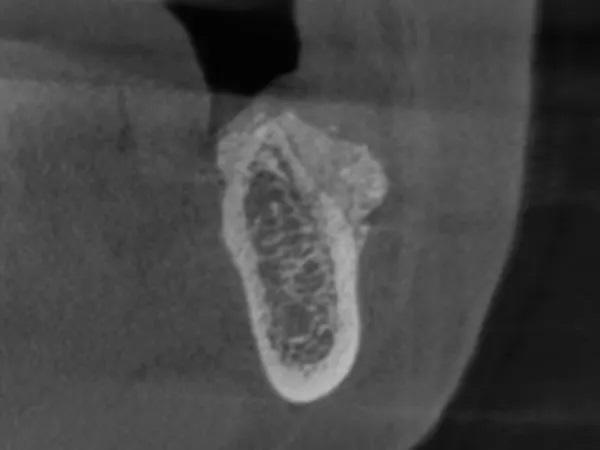

Женщина, 45 лет, с неотягощенным анамнезом, обратилась по поводу замены правого латерального резца верхней челюсти. После освобождения лоскута был выявлен сильный дефицит горизонтального гребня с остаточной шириной кости от 3 мм до 4 мм, что подтверждает данные КЛКТ (Фото 12 и Фото 13).

Фото 13: КЛКТ до операции, правый латеральный резец верхнечелюстной кости.